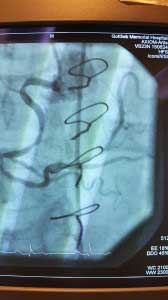

Interventional case 2